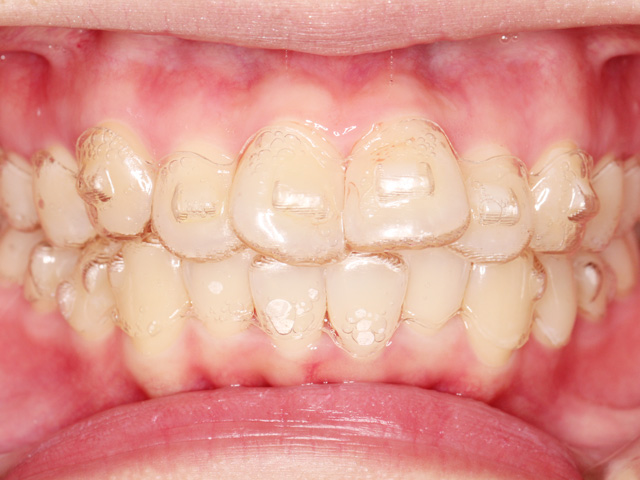

正面の画像です。上下の前歯に叢生が見られます。

上下とも中切歯(中央の前歯)よりも側切歯(中央から2番目の前歯)が内側に位置しています。特に左下の側切歯(中央から2番目の前歯)の叢生ははなり重度の状態です。